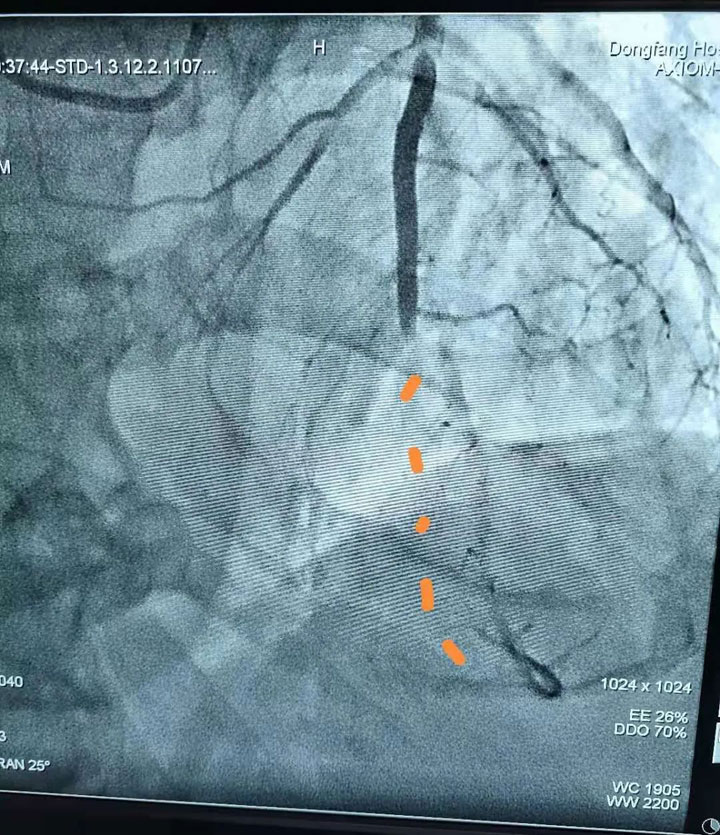

胸痛中心团队医生——心血管内科副主任王其虎、医生宁伟、熊堂鹏为患者施行了急诊冠状动脉造影+取栓术。术中造影发现患者心脏回旋支中端血管完全闭塞,大面积心肌没有血供,医生紧急使用取栓装置由远至近多次抽吸血栓,完成血运重建。“我们采用的这种取栓装置可以直接将大的血栓全部吸出体外,人体内将不再残留小血块,大大降低产生并发症的几率。”心血管内科医生熊堂鹏介绍说,这项技术可以免去冠脉支架的植入,即“介入无植入”,为广大冠心病患者提供了更加安全、有效的治疗手段。

患者闭塞的血管被及时打通,濒临坏死的缺血心肌又恢复了血供,胸痛中心团队的医生齐心协力、争分夺秒地从死神手里将患者的生命夺了回来。目前,患者已转入心血管内科CCU住院,状态良好,无胸闷痛、气短症状发作。